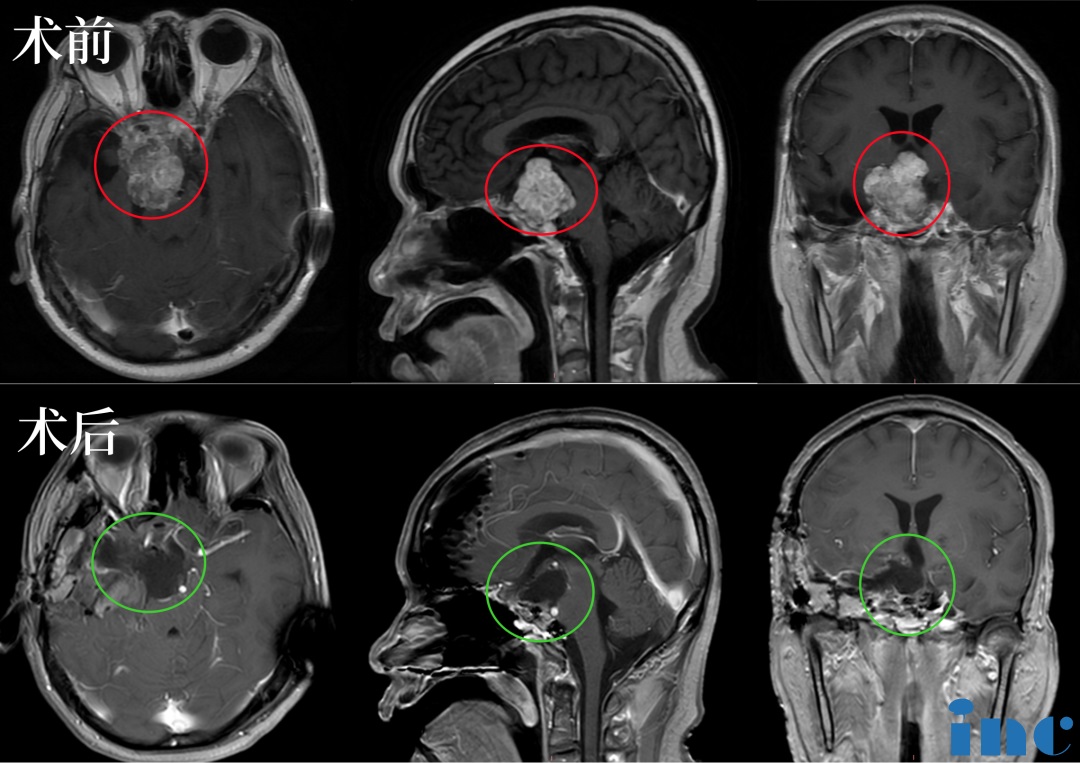

48岁的苏先生2019出现无明显诱因的视野缺损,伴视力下降,遂就诊当地医院。行颅脑磁共振检查,提示占位性病变,脊索瘤可能性大。2019年-2023年患病期间苏先生经历了4次复发3次手术,(两次经鼻内镜,一次开颅),一次脑积水分流术,近期肿瘤再次复发,症状再次加重,肿瘤位置在斜坡鞍区,包饶重要的椎基底动脉、动眼外展等神经,挤压三脑室,下丘脑、视神经等重要结构,手术难度较大。

术前:肿瘤体大,广泛累及颅底结构,侵蚀斜坡、鞍内鞍上、海绵窦区,包裹右侧颈内动脉。肿瘤向上推挤视神经、视交叉,到达三脑室底部;向后上方推挤脑干和基底动脉,部分肿瘤边缘与脑干分界欠清。

2023年5月,福教授应邀访问苏州大学附属独墅湖医院(苏州市独墅湖医院),苏先生抓住了这个机会,咨询福教授能否为自己手术,在经过一系列评估以及术前紧急补充激素等措施,2023年5月15日,INC法国福教授为苏先生做了四次开颅手术,在术中,福教授联合应用显微镜和内镜,运用的“筷子手法”,术后当晚核磁显示肿瘤已基本全切。这对夫妻是幸运的,在这场风险较大、具挑战的手术中重获新生。

术后:手术顺利,术中将鞍上鞍内、海绵窦区、三脑室肿瘤切除